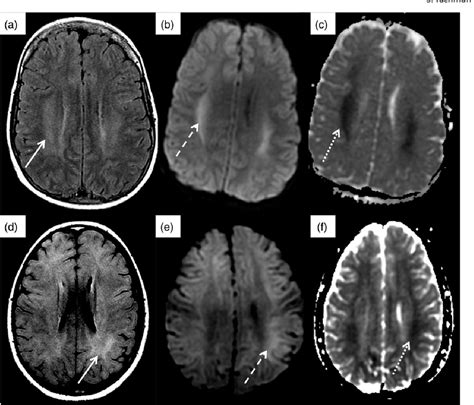

Dialysis Disequilibrium Syndrome is a neurological complication that can arise during or shortly after hemodialysis. It is characterized by a range of symptoms, including confusion, seizures, and in severe cases, coma. The syndrome occurs due to rapid shifts in fluid and electrolyte balance, which can lead to cerebral edema, or swelling of the brain.

DDS is more commonly observed in patients undergoing their first few dialysis sessions, particularly those with severe kidney failure who have not yet undergone regular dialysis. The rapid removal of urea and other waste products from the blood can cause an osmotic gradient, drawing water into the brain and leading to the symptoms of DDS.

• Use imaging studies, such as a CT scan or MRI, to visualize any swelling or abnormalities in the brain.